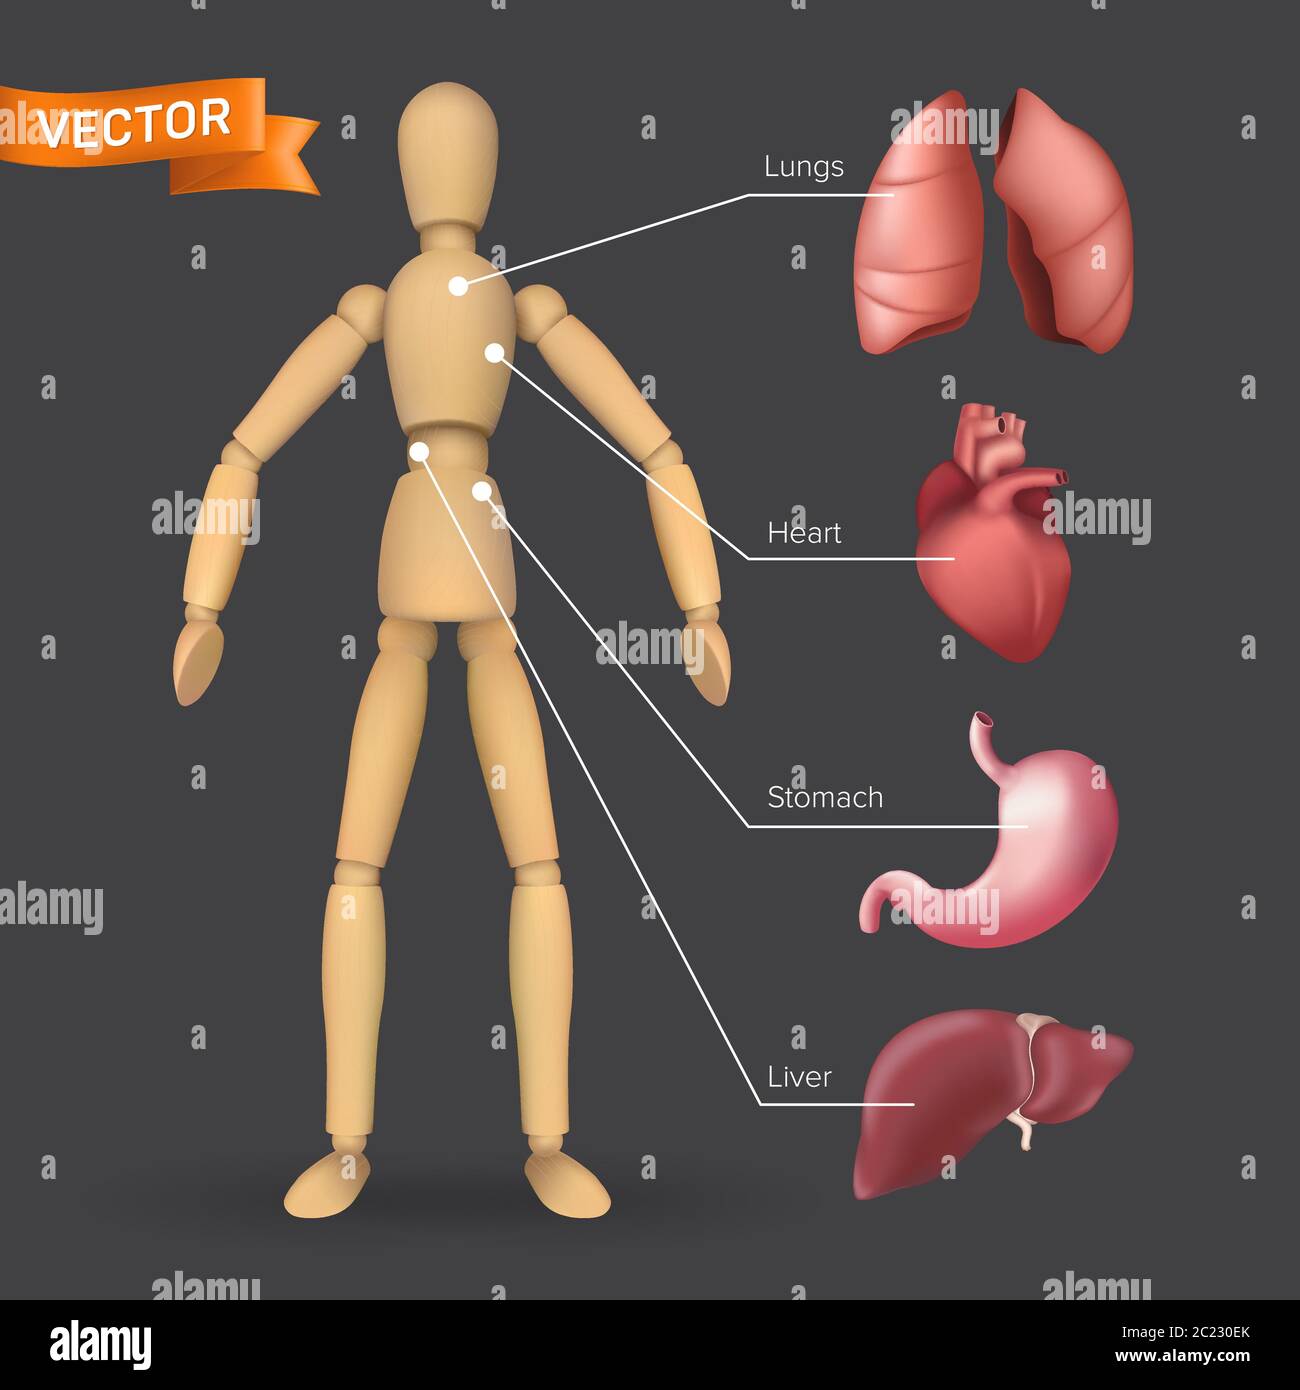

Infographie avec les organes internes humains : cœur, estomac, foie, poumons placés sur une silhouette de mannequin en bois mâle ou femelle. Illustration vectorielle de bo Illustration de Vecteurhttps://www.alamyimages.fr/image-license-details/?v=1https://www.alamyimages.fr/infographie-avec-les-organes-internes-humains-coeur-estomac-foie-poumons-places-sur-une-silhouette-de-mannequin-en-bois-male-ou-femelle-illustration-vectorielle-de-bo-image362713307.html

Infographie avec les organes internes humains : cœur, estomac, foie, poumons placés sur une silhouette de mannequin en bois mâle ou femelle. Illustration vectorielle de bo Illustration de Vecteurhttps://www.alamyimages.fr/image-license-details/?v=1https://www.alamyimages.fr/infographie-avec-les-organes-internes-humains-coeur-estomac-foie-poumons-places-sur-une-silhouette-de-mannequin-en-bois-male-ou-femelle-illustration-vectorielle-de-bo-image362713307.htmlRF2C230EK–Infographie avec les organes internes humains : cœur, estomac, foie, poumons placés sur une silhouette de mannequin en bois mâle ou femelle. Illustration vectorielle de bo